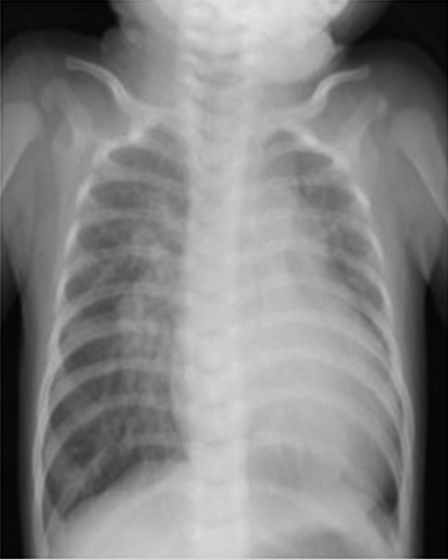

胸部レントゲン

心胸郭比63%,肺血管陰影の増強を認めた(Fig. 1).

Fig. 1 Chest X-ray on 1st admission